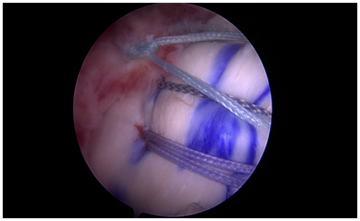

Tunnel bounded, minimal anchor hybrid repair (Figure 6): Tunnel bounded hybrid repair technique prioritizes tunnels as the primary fixation and allows for repair of any cuff tear with at least a single anchor and multiple tunnels using a reusable device, creating a high value repair with five fixation points. A double or triple anchor is placed at the center of the repair construct. Two tunnels are placed at the anterior and posterior margins of the tear. Three sutures are placed in each tunnel. After passing all sutures through the tendon, the anchor sutures are tied at the medial margin of the repair site. A passing suture is used to shuttle the medial anchor sutures through the lateral tunnels in the inferior to superior direction, reconstructing the footprint as in a transosseous equivalent repair, without the need for extra lateral anchors. These sutures are then tied back to themselves, creating a medial mattress component with fixation to the anchor. The remaining simple transosseous sutures are then tied, using the lateral suture limb as the post. Only one anchor is used in this construct at the point of medial stress concentration, while the footprint is restored using circumferential compression sutures without the need for more lateral anchors. As many other single tunnels may be added as necessary to augment the repair. The medial tails of the sutures may then by incorporated into a secondary backup lateral anchor if desired, creating a double anchor hybrid repair (Figure 7). Anchors and tunnels are thus used synergistically to maximize repair integrity and minimize cost.

Figure 6 Single anchor: example of a tunnel bounded repair with a single anchor medially. Footprint reconstruction is achieved without the need for lateral anchors.

Figure 7 Tunnel bounded, double anchor repair: one medial and one lateral anchor are utilized with two tunnels, creating six fixation points.